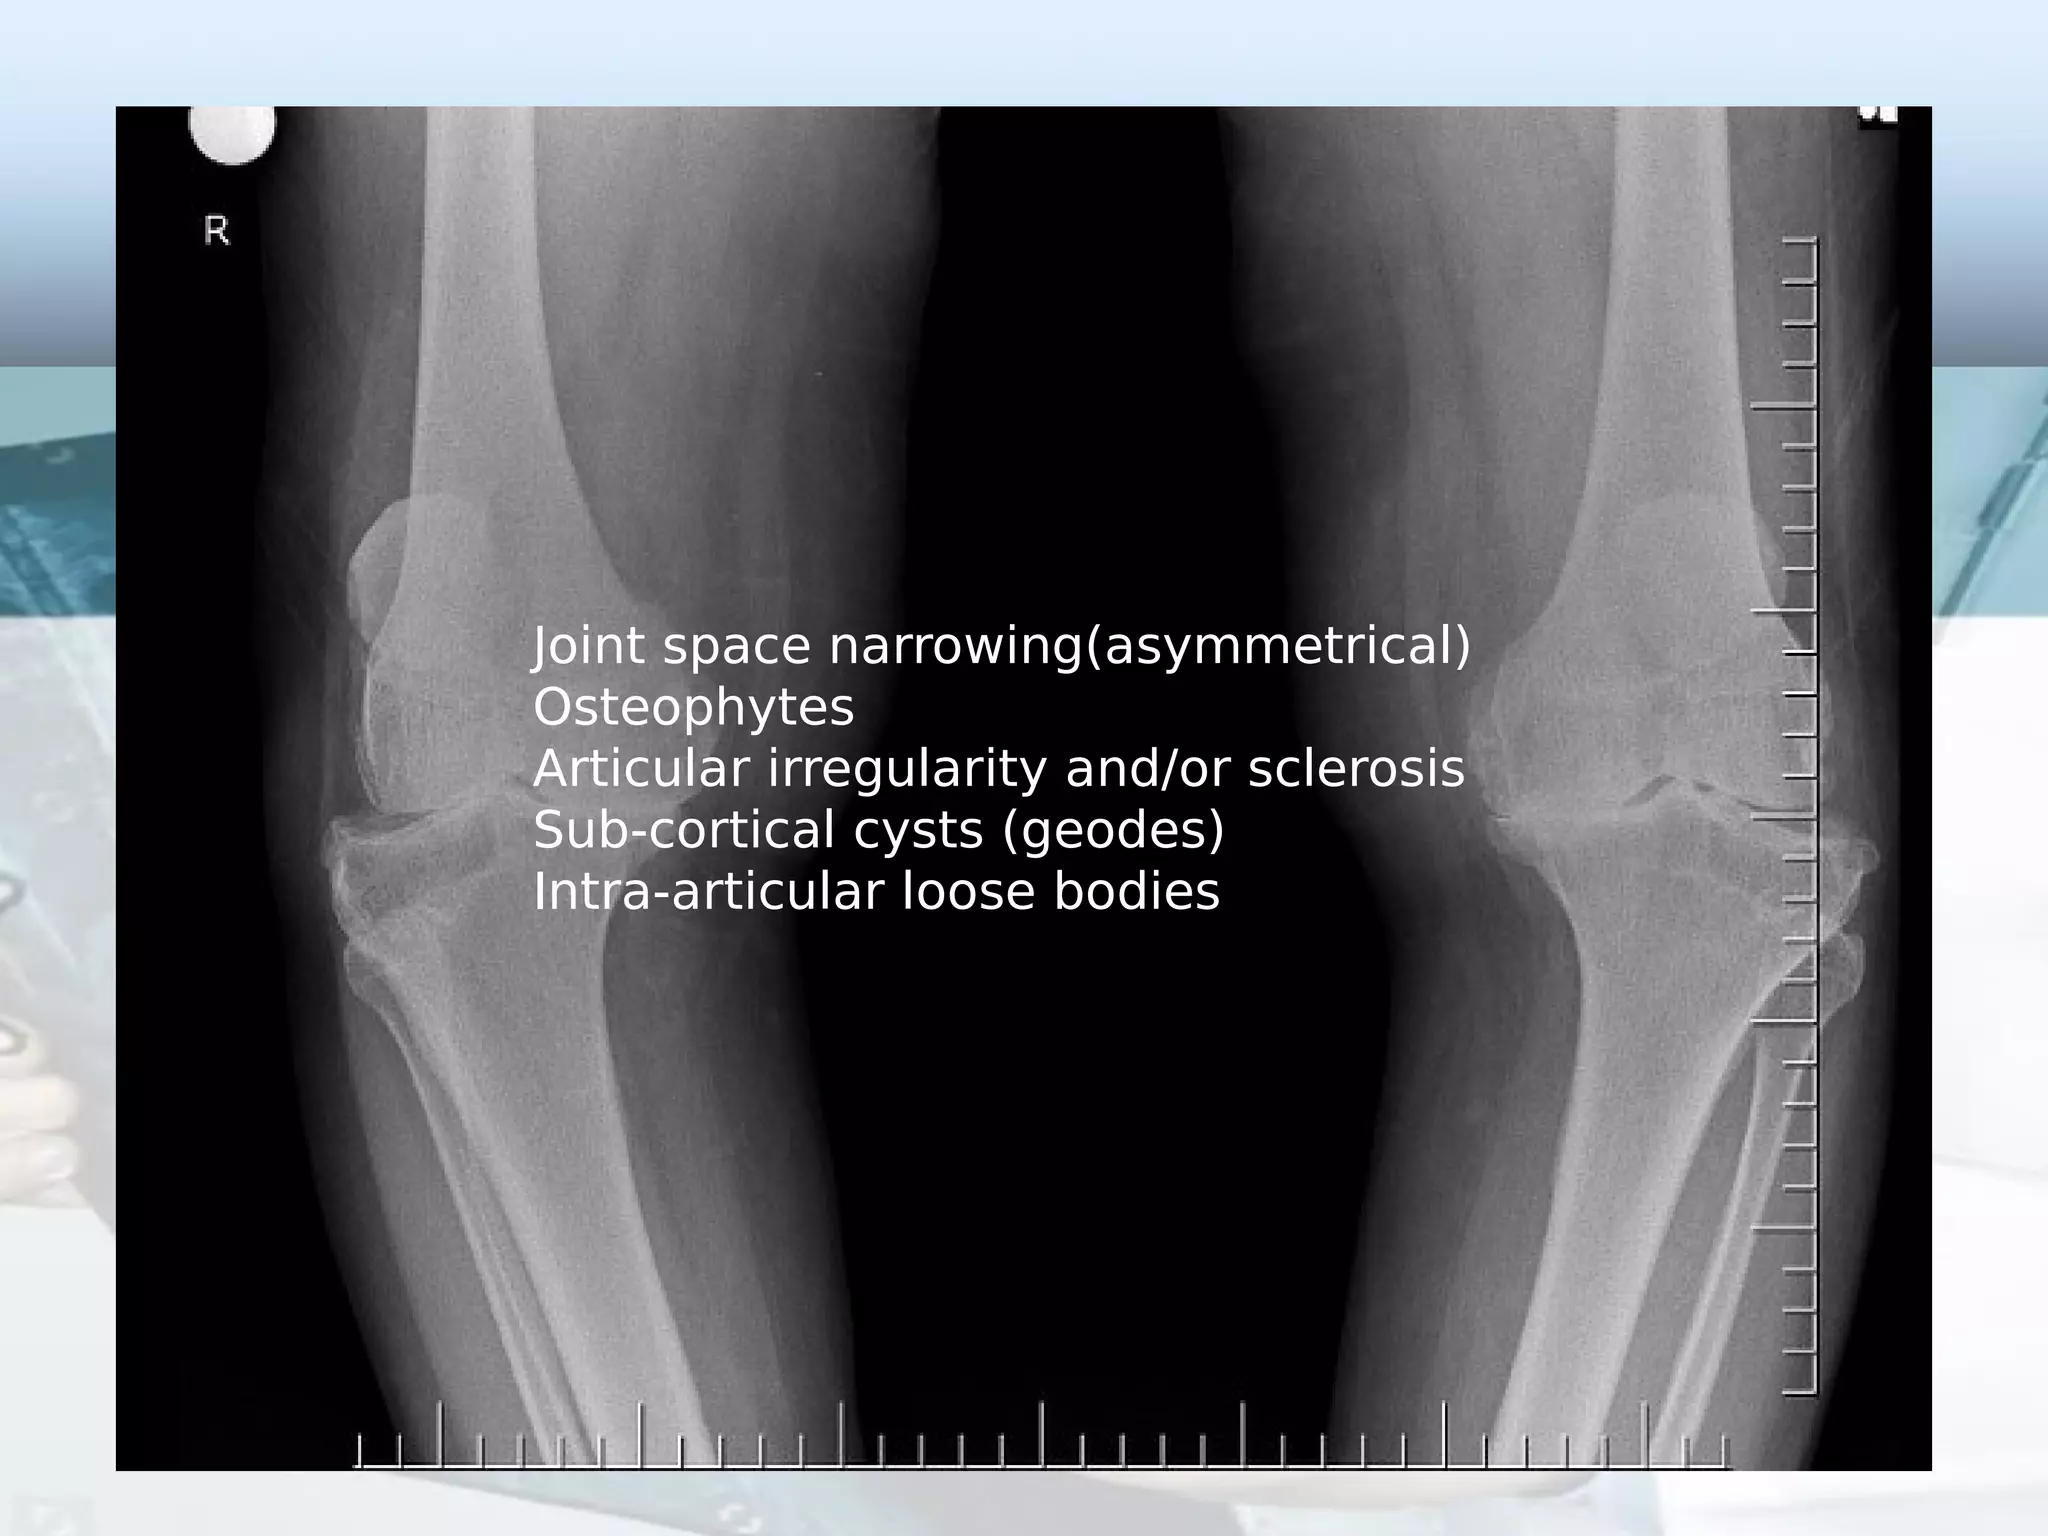

Osteophytes Knee